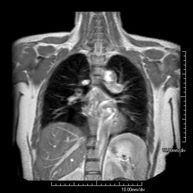

Prova diagnòstica no invasiva que consisteix en l'obtenció d'imatges d'alta definició anatòmica del mediastí mitjançant l'ús d'un camp electromagnètic i ones de ràdio (amb un emissor i un receptor). No utilitza radiació ionitzant. El mediastí és la part central de la caixa toràcica que inclou el tim, els grans vasos (aorta toràcica, vena cava inferior i superior, etc.), el cor, la tràquea i els bronquis principals, els ganglis limfàtics mediastínics i hilars, l'esòfag, etc. Està especialment indicada en lesions mediastíniques per diferenciar si són quístiques o sòlides, en el diagnòstic diferencial de les lesions del mediastí anterior, etc. De vegades s'ha d'emprar contrast paramagnètic (Gadolini) per completar l'estudi. - RM Tòrax

Prova diagnòstica no invasiva que consisteix en l'obtenció d'imatges d'alta definició anatòmica del tòrax mitjançant l'ús d'un camp electromagnètic i ones de ràdio (amb un emissor i un receptor). No utilitza radiació ionitzant. Està indicada en aquelles lesions pulmonars en les quals s'ha de descartar si hi ha infiltració del mediastí o de la paret toràcica, per diferenciar si una lesió toràcica és sòlida o quística, etc. En alguns casos caldrà emprar contrast paramagnètic (Gadolini) per completar l'estudi. - RM de Paret Toràcica

- RM Tórax

Prueba diagnóstica no invasiva que consiste en la obtención de imágenes de alta definición anatómica del tórax mediante el empleo de un campo electromagnético y ondas de radio (con un emisor y un receptor). No utiliza radiación ionizante. Está indicada en aquellas lesiones pulmonares en las que debe descartarse si existe infiltración del mediastino o de la pared torácica, para diferenciar si una lesión torácica es sólida o quística, etc. En ocasiones se deberá emplear contraste paramagnético (Gadolinio) para completar el estudio. - RM Abdomen